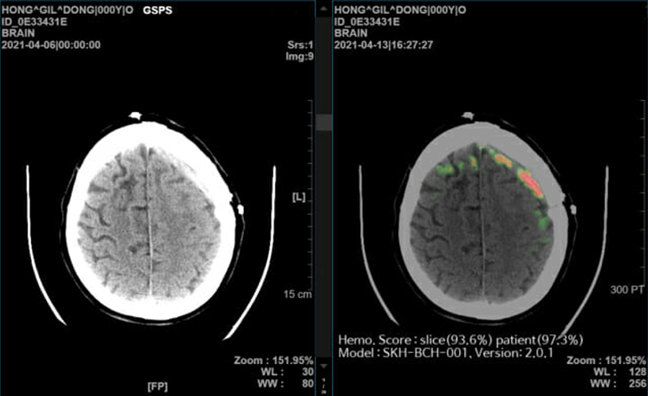

주요 제품인 ‘메디컬 인사이트 플러스 뇌출혈’은 뇌 CT 영상을 수초 내 분석해 98%의 정확도로 출혈 위치와 이상 여부를 의료진에게 알려주는 서비스로, 뇌출혈 환자의 골든타임을 단축시키고 진단 정확도를 높여 응급실에서의 진료 효율성을 개선하는 효과가 다수의 임상 연구에서 입증되었다. 이 기술은 보건복지부의 혁신의료기술로 지정되었으며, 미국 FDA 품목 허가도 취득한 바 있다.

The main product, 'Medical Insight Plus Cerebral Hemorrhage', is a service that analyzes brain CT images within seconds and informs medical staff of the location of the hemorrhage and any abnormalities with 98% accuracy. It has been proven in numerous clinical studies to be effective in shortening the golden time for cerebral hemorrhage patients, increasing diagnostic accuracy, and improving treatment efficiency in emergency rooms. This technology has been designated as an innovative medical technology by the Ministry of Health and Welfare, and has also obtained product approval from the US FDA.